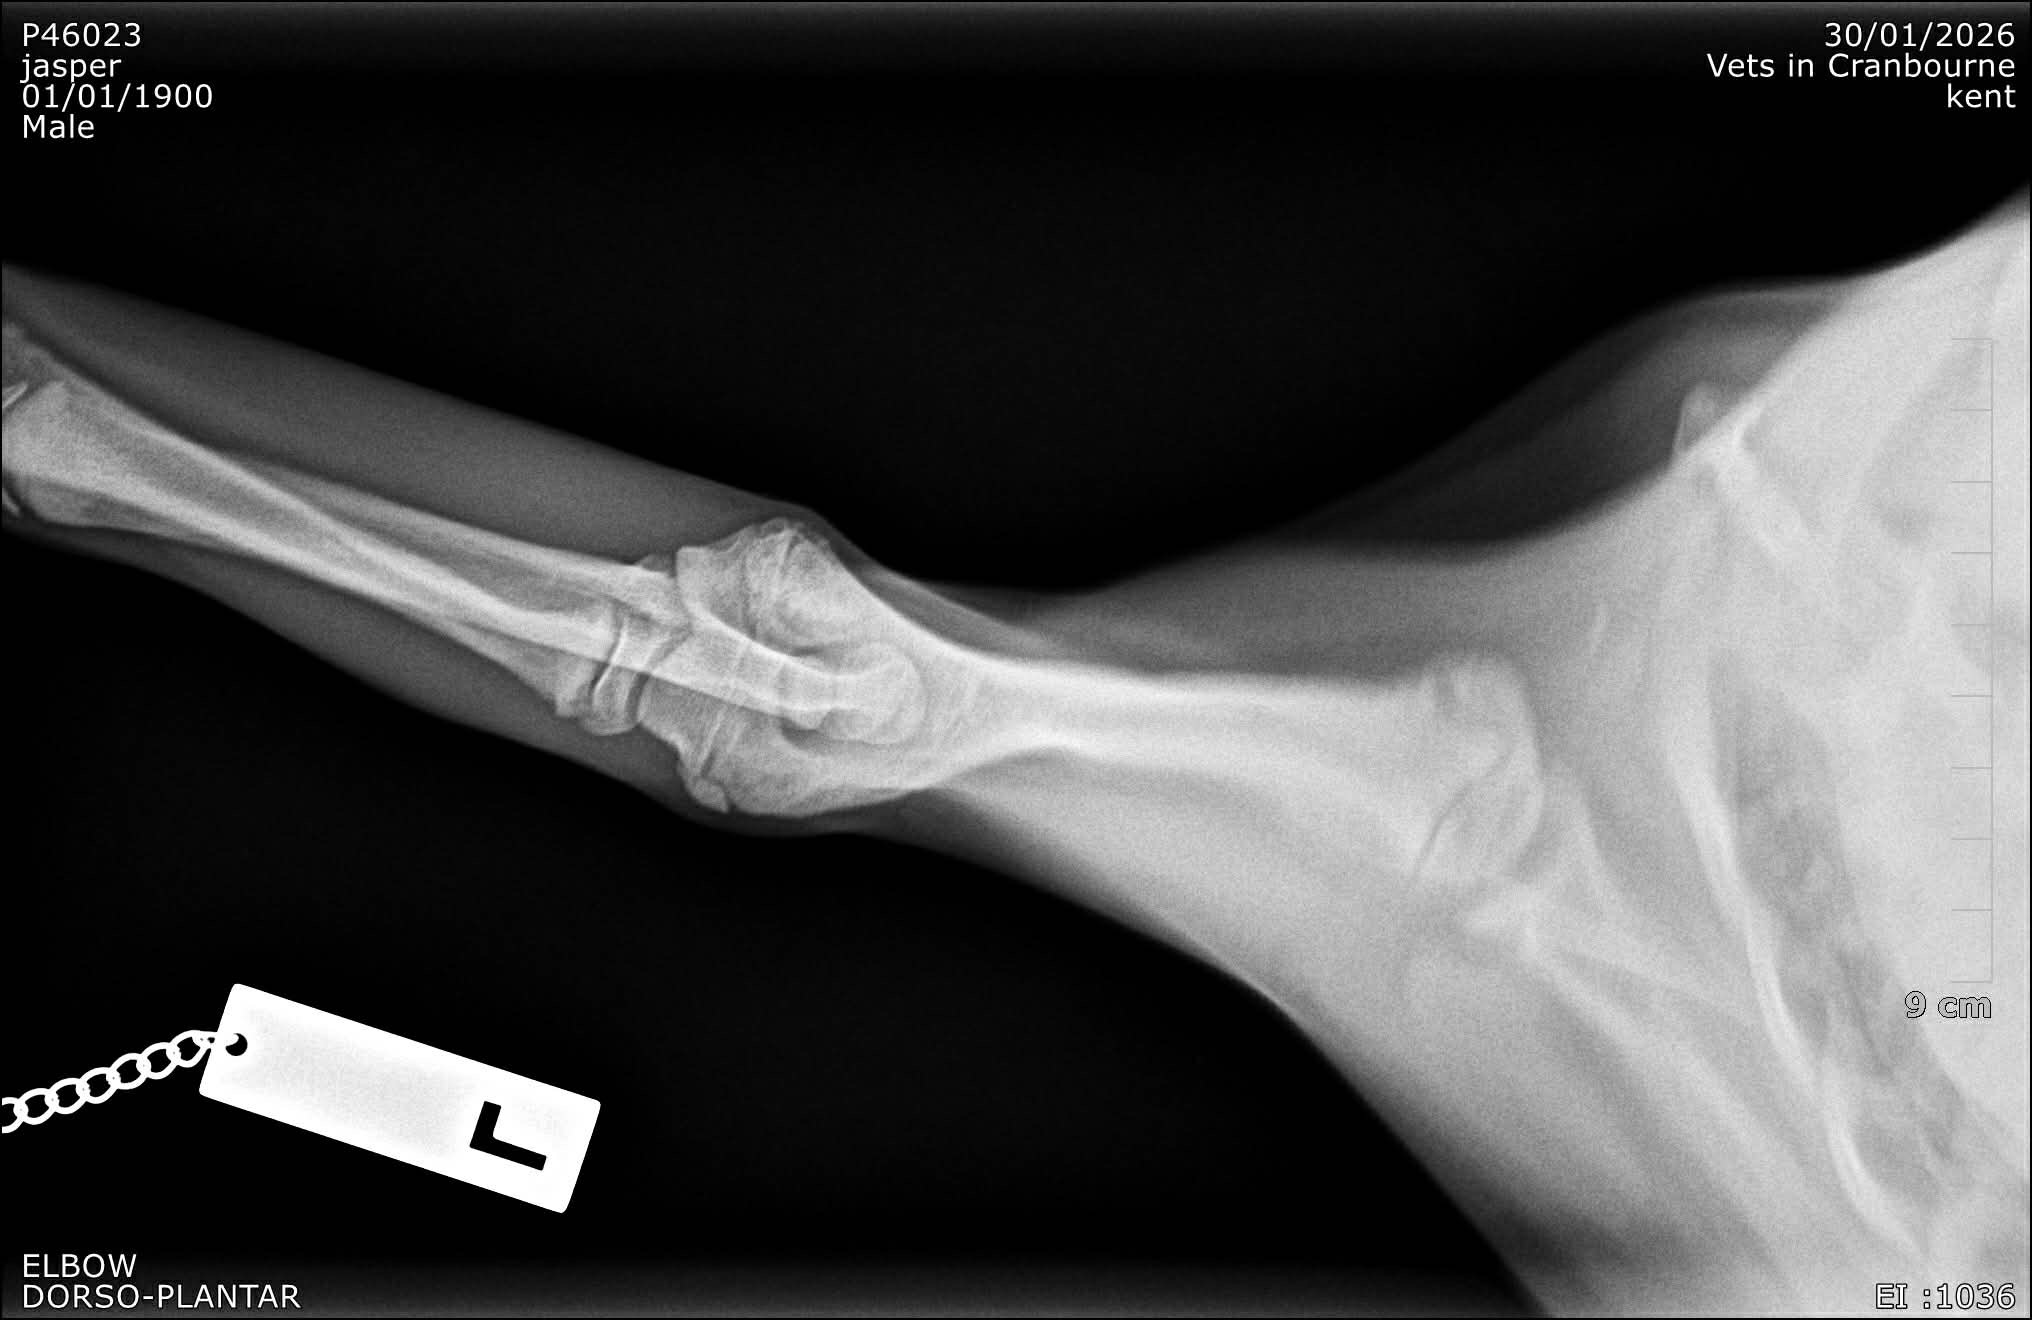

When Nemo was younger he suffered a growth plate injury, something that can happen in a split second during normal puppy play. Unfortunately, as he continued to grow, the damaged growth plate caused his leg to develop incorrectly and begin turning outward.

What started as a small injury has now developed into a significant orthopaedic problem affecting how he stands and walks.

Today Nemo underwent a corrective osteotomy performed by specialist surgeon Ben Mielke.

This procedure involves surgically cutting and realigning the bone so his leg can grow and function more normally. It is a complex surgery, but it gives Nemo the best possible chance at living a comfortable and active life.